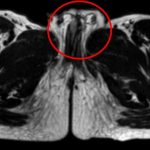

Da legene undersøkte gutten, viste det seg at gutten hadde to fullt utviklede peniser med samme forhud.

Sjuåringen var i stand til å tisse med begge penisene.

Ifølge kirurgene kan denne tuberkelen enten «dele seg» i to falloser, slik at hver fallos har sin egen kropp og sitt eget urinrør.

Eller så kan den splitte seg, slik at hver fallos har to svamplegemer og to urinrør. En dobbel penis kommer imidlertid sjelden uten utfordringer: